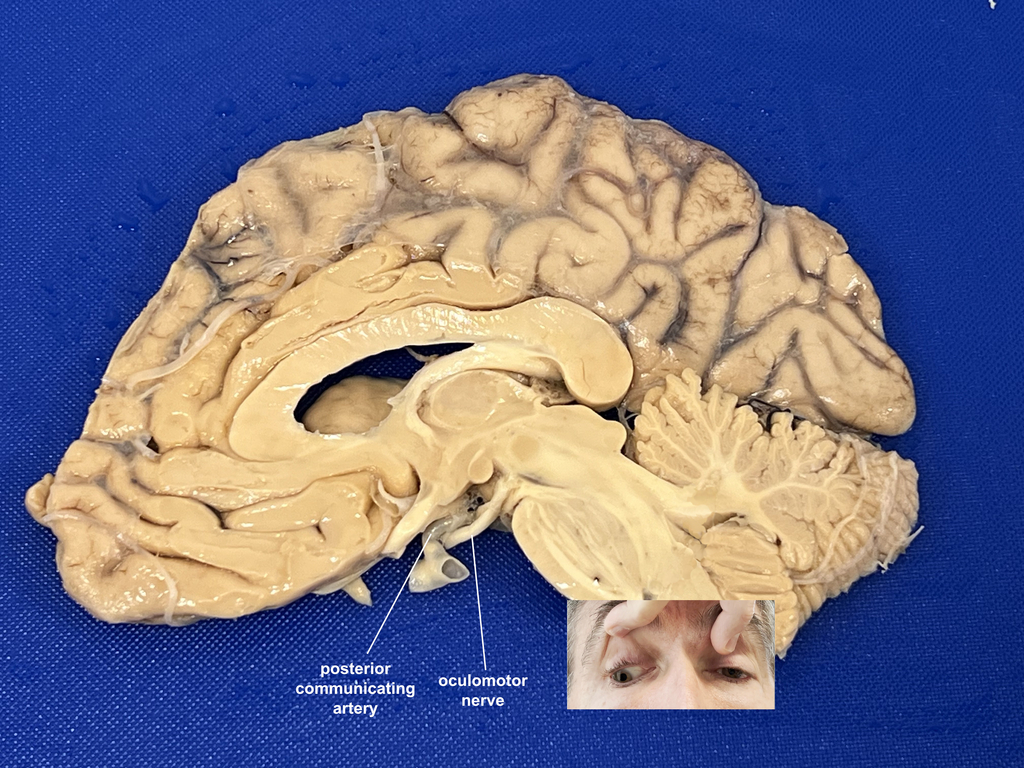

An aneurysm of the posterior communicating artery compresses CN III causing an oculomotor palsy (note the close association of the PCom artery and the oculomotor nerve.) This can begin with just parasympathetic injury causing a "blown" or dilated pupil which can be the red flag to check for such an aneurysm so it can be treated before rupturing causing what type of intracranial bleed? Recall that the arteries are all with the CSF, beneath the arachnoid mater. Hence, it would be a subarachnoid bleed. To appreciate these layers and the relationship between the posterior communicating artery and the oculomotor nerve, watch the brain removal video.As for this case, remember that an oculomotor palsy causes first a blown pupil, then a "down and out" appearance. Return to the case to try again.